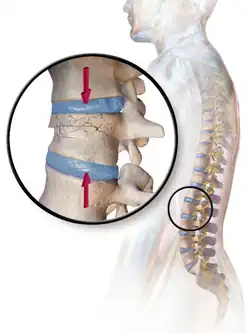

A compression fracture is a collapse of a vertebra. It may be due to trauma or due to a weakening of the vertebra (compare with burst fracture). This weakening is seen in patients with osteoporosis or osteogenesis imperfecta, lytic lesions from metastatic or primary tumors,[1] or infection.[2] In healthy patients, it is most often seen in individuals suffering extreme vertical shocks, such as ejecting from an ejection seat. Seen in lateral views in plain x-ray films, compression fractures of the spine characteristically appear as wedge deformities, with greater loss of height anteriorly than posteriorly and intact pedicles in the anteroposterior view.[3]

Compression fractures are usually diagnosed on spinal radiographs, where a wedge-shaped vertebra may be visible or there may be loss of height of the vertebra. In addition, bone density measurement may be performed to evaluate for osteoporosis. When a tumor is suspected as the underlying cause, or the fracture was caused by severe trauma, CT or MRI scans may be performed.